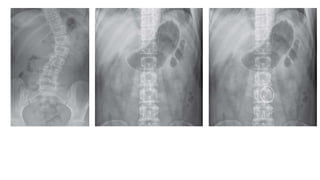

DILATED LARGE BOWEL

Bowel proximal is dilated and distal is collapsed.

Causes:

1. malignancy ( colorectal carcinoma- MCC in adults)

2. diverticular stricture

3. faecal impaction

4. volvulus.

Radiographic appearance:

1. dilatation >5.5cm – caecum is allowed to reach

9cm before being called dilated.

2. circumferential location- peripherally located .

Exception is transverse colon – loops down towards

pelvis and can cross centre of the radiograph.

3. haustra : small pouches in the wall of LI. Taenia

coli (ribbons of smooth muscle which run along the

length of the colon) are shorter than the colon itself,

therefore the colon becomes sacculated between the

taenia coli forming the haustra.

Lines between the haustra are called haustral folds

and do not cross the entire width of the bowel

If the bowel is grossly distended, then the haustra

may not be seen.